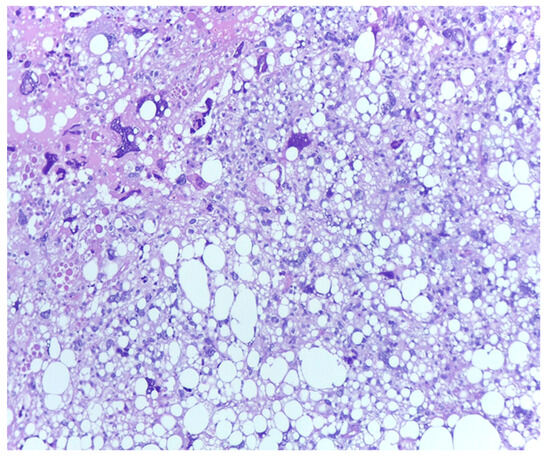

3.1. Tumor Grade

- Ciongariu, A.M.; Țăpoi, D.A.; Dumitru, A.V.; Bejenariu, A.; Marin, A.; Costache, M. Pleomorphic Liposarcoma Unraveled: Investigating Histopathological and Immunohistochemical Markers for Tailored Diagnosis and Therapeutic Innovations. Medicina 2024, 60, 950. [Google Scholar] [CrossRef] [PubMed] [PubMed Central]